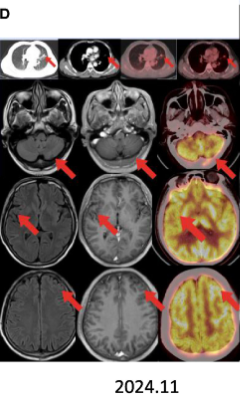

疗效评估

术后继续予伏美替尼辅助治疗,随访至2025年5月(术后18个月),头颅MRI示无复发灶,肺部及脑部均未发现肿瘤复发。

本病例患者携带EGFR敏感突变与MEK1复合突变,且PD-L1高表达,提示其对靶向、免疫及化疗联合治疗可能具有良好应答。伏美替尼作为第三代EGFR-TKI,在FURLONG研究中显示出优越的颅内病灶控制能力。替雷利珠单抗在RATIONALE-307研究中亦证实与化疗联用可延长无进展生存期(PFS)。

尽管神经外科与放疗科医生曾建议脑部放疗,患者最终接受了“化疗+免疫治疗+靶向治疗”三联方案,并在未接受局部治疗的情况下实现脑转移灶完全缓解。这表明,在部分经过选择的患者中,系统性治疗可作为脑转移的有效初始治疗手段。